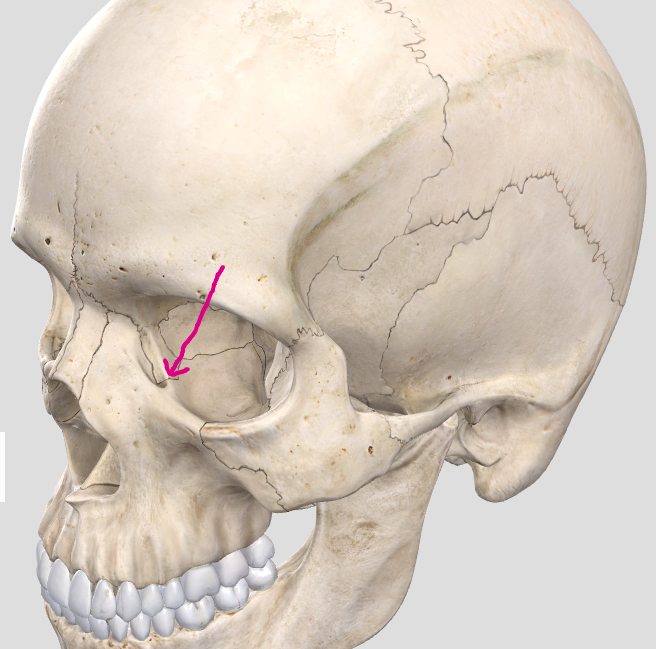

Greater wing of the sphenoid bone (“sphen”=wedge)

Greater wing of the sphenoid bone (“sphen”=wedge)

Zygomatic process (helps form zygomatic arch with the zygomatic bone)